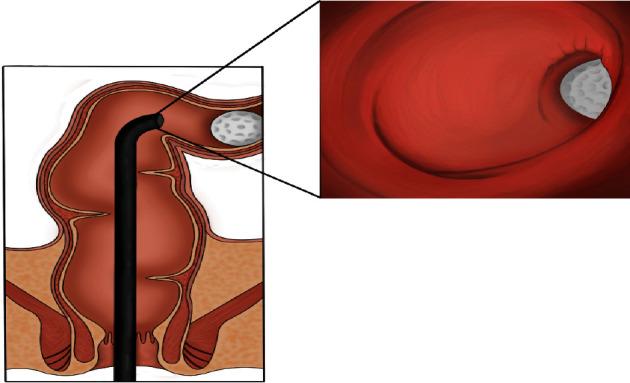

Rectal foreign bodies form a surprisingly frequent cause of presentation to the emergency department. The materials inserted constitute a wide range of size, shape, and texture with each presenting a unique set of challenges. Despite a seemingly innocuous presentation, if not recognised early and managed accordingly, significant complications can develop including obstruction, perforation, and sphincteric injury. The existing doctrines advocate endoscopic intervention after simple measures fail and advise against the use of laxative therapy due to concerns for complications that may arise. The authors of this study challenge this notion, provided certain conditions are met. . We report the case of a 14-year-old boy who inserted a golf ball into his rectum, which subsequently migrated proximally into the sigmoid colon on plain radiographic films. The patient was asymptomatic on presentation, and there was no clinical evidence of bowel injury or mechanical bowel obstruction. Endoscopic removal of the golf ball was pursued under general anaesthesia. Despite protracted efforts, the golf ball was not able to be retrieved endoscopically. In an attempt to avoid aggressive surgery, volume laxatives were administered with successful passage of the golf ball several hours later.

This case discusses the unique technical challenges, which may be encountered when attempting to retrieve a large, spherical, and non-confirming foreign body entrapped above the rectosigmoid junction and how these factors can complicate endoscopic retrieval. The authors advocate that in the absence of a mechanical bowel obstruction, patients with foreign bodies possessing physical properties that are amenable to spontaneous passage, a trial of strong aperients, should be considered first line. The author's contention is that direct escalation to removal of foreign body in theatre can be resource draining and may expose the patient to additional risk.

直肠异物是急诊就诊的一个出人意料的常见原因。插入的物品在大小、形状和质地方面多种多样,每种都带来一系列独特的挑战。尽管临床表现看似无害,但如果早期未被识别并进行相应处理,可能会出现严重并发症,包括梗阻、穿孔和括约肌损伤。现有理论主张在简单措施失败后进行内镜干预,并因担心可能出现的并发症而建议不要使用泻药疗法。本研究的作者对这一观点提出了质疑,前提是满足某些条件。我们报告了一名14岁男孩的病例,他将一个高尔夫球插入直肠,随后在平片上显示该球向近端迁移至乙状结肠。患者就诊时无症状,也没有肠道损伤或机械性肠梗阻的临床证据。在全身麻醉下尝试通过内镜取出高尔夫球。尽管经过长时间努力,但仍无法通过内镜取出该球。为避免进行激进手术,给予了大容量泻药,数小时后高尔夫球成功排出。

本病例讨论了在试图取出嵌顿于直肠乙状结肠交界处上方的大型、球形且形状不规则的异物时可能遇到的独特技术挑战,以及这些因素如何使内镜取出复杂化。作者主张,在没有机械性肠梗阻的情况下,对于异物的物理特性适合自然排出的患者,首先应考虑试用强效缓泻剂。作者的观点是,直接升级为在手术室取出异物可能会消耗资源,并可能使患者面临额外风险。